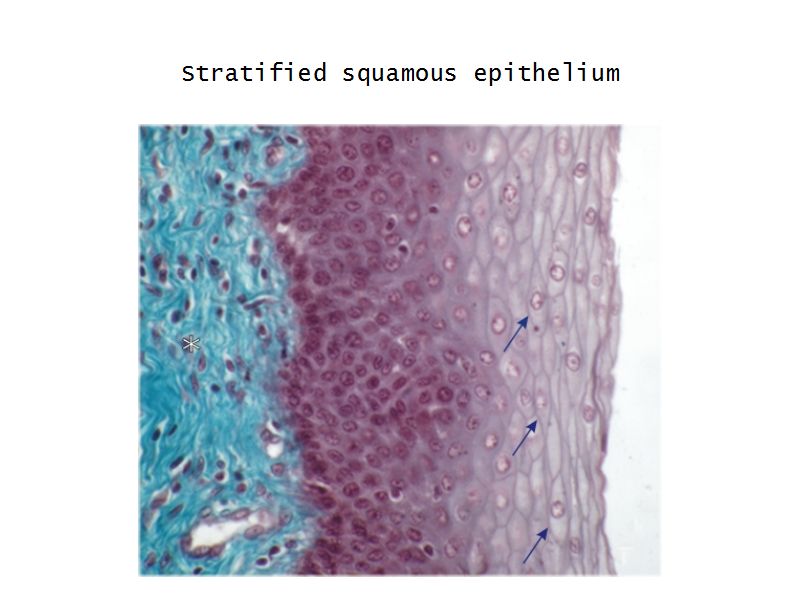

Vagina

Slide 90

Vagina

- Fibromuscular tube with 3 layers

- Inner mucosa

- Middle muscle layer

- External adventitia

Fibro = fibrous tissue

Muscular = muscle tissue

Tube = epithelium

Mucosa

- Epithelium

- Thick stratified squamous nonkeratinized

- Lamina propria

- Fibroelastic connective tissue

- Rich in elastic fibres

- Contains lymphoid elements

- Deep portion highly vascular

- No glands